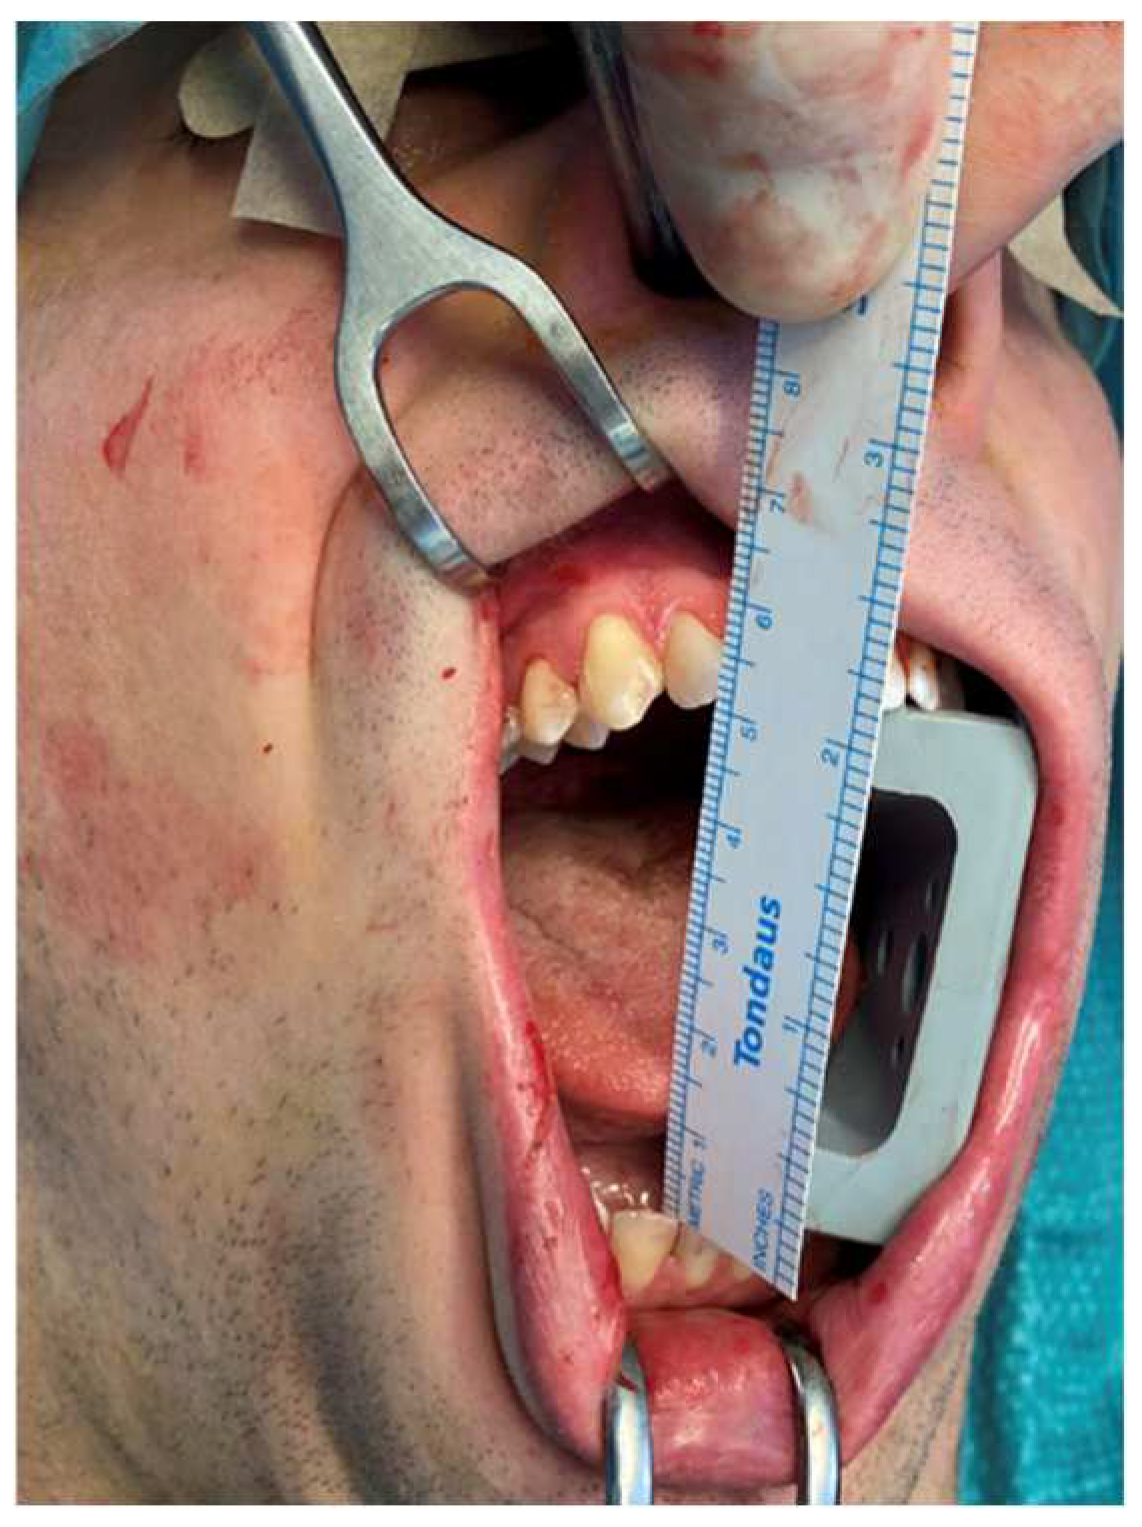

Figure 5.

Patient showing an MMO of 20 mm and a slight deviation to the right at first physical examination.

An 18-year-old male patient with a 24-month history of worsening reductions in mouth opening was referred to our attention for an evaluation of suspected TMD. No previous history of trauma was reported by the patient, and the medical history did not report any relevant elements. A physical examination showed an MMO of 20 mm with a deviation to the right during mouth opening (Figure 5). The patient did not complain of pain at the palpation of TMJ bilaterally. The masticatory muscles were painful bilaterally and especially on the right side. No TMJ clicking or crepitus were detectable. The endfeel was rigid and painful on the right side. At the OPG, the right glenoid fossa and condyle were not totally distinguishable, so an MRI and CT scan were requested to examine the case in depth. The MRI was negative for TMD, but in the CT scan, an enlarged right CPM with a mushroom-shaped end was highlighted, establishing a close relationship with the inner aspect of the right zygoma, which seemed impressed by the CPM forming a pseudojoint (Figure 6). It is interesting to notice how also the contralateral CPM was slightly elongated (Figure 7). The suspected diagnosis was of a right JD. The patient was subsequently submitted to an intraoral right coronoidectomy under general anesthesia. An incision along the vestibular aspect of the ascending mandibular ramus was performed, then a sub-periosteal dissection exposing the right maxillary zygomatic arch and the anterior rim of the mandibular ascending ramus was executed. At this point, the CPM was detected as showing a protuberance covered with fibrous tissue mimicking a capsule. Immediately after the completion of the coronoidectomy, the MMO increased to 40 mm (Figure 8). The histopathology of the CPM showed sections of compact, trabecular bone tissue covered by a layer of hyaline cartilage and fibrous cartilage overlaid by dense fibrous connective tissue—compatible with the diagnosis of osteochondroma (Figure 9). At 1 week, postoperative jaw-opening exercises and articular physiotherapy with TheraBite jaw motion rehabilitation system TM (Atos medical, Padua, Italy) were prescribed. At 1 month follow-up, the patient had an MMO of 20 mm, 18 mm at 2 months and 10 mm at 3 months. The cause of this negative trend was initially identified as the fibrotic retraction of the intraoral scar of the surgical access. At 5 months follow-up, the MMO was 32 mm and increased to 38 mm 1 month later. At 12 months follow-up, the MMO was 44 mm. A control CT scan was conducted and showed no recurrence and no significant changes on the contralateral side.

JD is a rare condition in which an elongated CPM interferes with the inner surface of the zygomatic arch, establishing a pseudojoint. In our review, which represents, possibly, the widest review in the literature, we report a mean age of 28.7 years old (5–73), with a difference in the age of incidence of almost 10 years between the two genders (25.7 years-old for males and 35.4 years old for females). In 12 cases, it was not possible to trace back the age of diagnosis of JD. We collected the data of 71 males (61.2%) and 34 females (29.3%). Unfortunately, 11 patients’ genders were not reported. These data are in agreement with what was previously reported in the literature, as affecting mainly men between the second and fourth decade [6]. An overall prevalence of 0.5% has also been reported, but this data could be underestimated because the onset of symptoms, such as limited mouth opening, represents just the endpoint of a longer-term development [55]. The left side is reported to be the most affected [7], which is confirmed by our analysis, in which we identified 38 cases of right JD (32.8%), 50 of the left side (43.1%) and 21 bilateral cases (18.1%). For seven cases, we were unable to retrieve information about the side of the defect. As mentioned before, JD usually remains relatively asymptomatic in its first stages, with most patients reporting only a sensation of tension during chewing. Then, it usually evolves with the limitation of mandibular movements and worsening reduction in MMO. In the reviewed cases, the mean MMO before surgical treatment was 13.9 mm (2–51). Sometimes, a distortion in the zygomatic arch projection on the affected side or a palpable moving hard mass perceptible during mandibular movements are present, particularly if JD is caused by an osteochondroma [94]. In unilateral cases, deviation to the affected side during mouth opening can be seen [75]. Pain or paresthesia are not often reported. This insidious clinical onset may be confused with several disorders such as TMD mainly, trauma arthrosis and various other causes of intra- and extra-articular ankylosis. Therefore, JD is also often mistreated. The etiology of the disease has already been widely debated. Some authors theorize a genetic or endocrine cause, and others suggest a role for temporalis muscle hyperactivity, trauma, TMJ disc displacement or a family predisposition, but it is mostly considered idiopathic [3,52,112]. Although the cause remains unknown, some authors reported periosteal hyperactivity as a trigger for ectopic metaplastic cartilage formation [5]. As stated before, according to the different amounts and patterns of bone and cartilage tissues present, the abnormally enlarged CPM can be histologically diagnosed as OC, CCE, CH, benign tumors (such as osteoma or chondroma) or other developmental anomalies [4,7,10,14,70]. We found 17 cases of CCE (14.7%), 10 cases of CH (8.6%) and 76 cases of OC (65.5%), while in 13 cases (11.2%), it was not possible to establish a definite histological diagnosis. This marked prevalence of OC as a cause of JD may partly explain the confusion over its definition and its almost exclusive bi-directional association with pathology reported by various authors. It is also interesting to note how this pathology shows different clinical and radiological patterns, leading to a wide spectrum of presentations. Considering, for example, the cases we have reported, it is possible to see how they present a pattern of increasing severity from the first to the third patient. The first patient presented an early pathologic radiological pattern, with the pseudojoint not yet fully formed with an MMO of 25 mm. It should be remembered that ankylosis, in this case, extra-articular, is established when the MMO is less than 15 mm, and this is considered an incomplete ankylosis, when the MMO is less than 5 mm, the ankylosis is complete [113,114]. In contrast, the second patient showed a well-established ipsi-pseudo-articular framework and an MMO of 20 mm. In this patient, it is also interesting to notice how the contralateral CPM was also slightly longer than normal, although not yet pathological. The third patient, on the other hand, showed a well-established bilateral pattern with perfectly developed pseudojoints and a rapidly worsening 20 mm MMO. Our experience and analysis of the literature prompted us to wonder whether it was possible to classify, according to clinical and radiological features, the vast pathological spectrum that JD expresses. We, therefore, designed a classification proposal, as shown in Table 2, in order to speculate on the possibility of assigning an index of severity and stage to the various connotations of JD. Obviously, this classification has to be intended as a proposal, considering that more cases have to be analyzed to evaluate its possible validity.